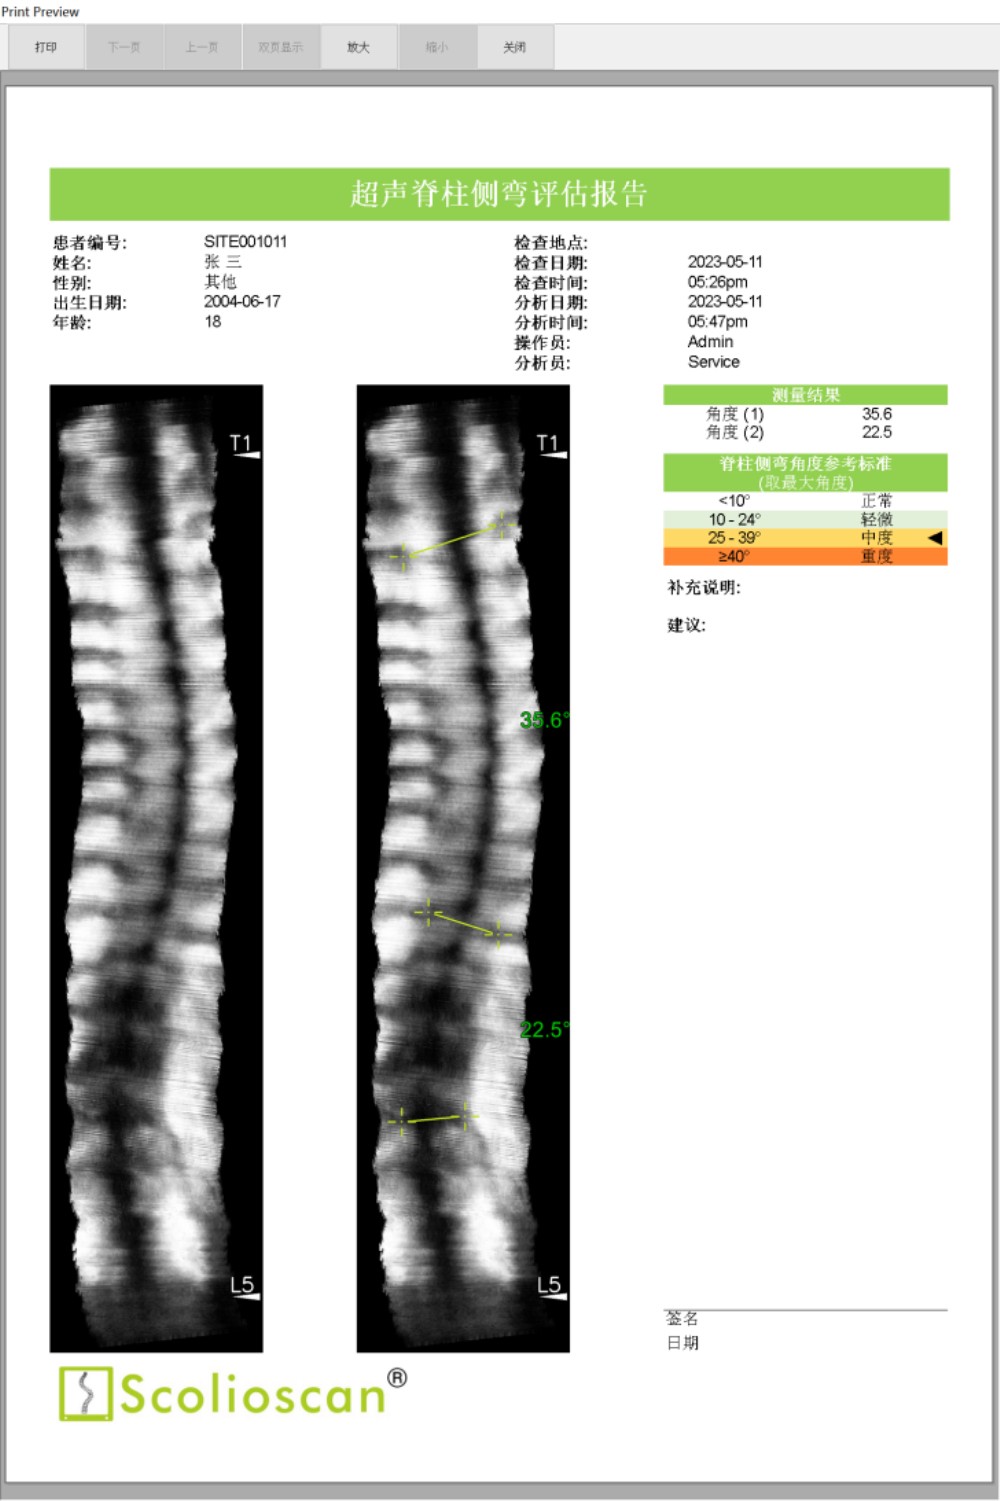

临床试验结果显示,Scolioscan®的测量结果与X光成像高度一致,线性相关度达到0.9464。使用Scolioscan®及早发现青少年的脊柱侧弯问题后,医生得以把握宝贵的黄金治疗时机,通过非手术方式有效控制和治愈疾病,实现早诊断、早治疗、早康复。

脊柱侧弯的恶化速度较快,在青春期生长突增时期,侧弯曲线以每个月1-2度的速度恶化,因此有必要对患者病情进行较为频繁的跟踪监测。脊柱侧弯患者在整个青春发育期大约需要接受10次以上的X光检查,有研究表明脊柱侧弯患者的总体癌症发病率是同龄人口的5倍。由于Scolioscan®能够避免X光辐射的风险,因此我们可以打破常规,实现安全频密的病情追踪和及时的疗效评估。

内蒙古自治区首台“Scolioscan®无辐射三维超声脊柱侧弯评估系统”成功引入91直播 ,可广泛应用于脊柱侧弯筛查、诊断、病情跟踪和预测以及非手术治疗阶段对治疗结果的可视化反馈和评价等多个领域,为广大儿童青少年提供精准度媲美X光的无辐射、安全的脊柱侧弯评估方案,帮助患有脊柱侧弯的孩子早发现、早干预、早康复,竖起脊梁健康成长。